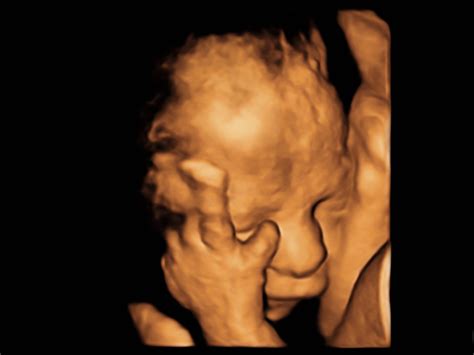

Okrem OGTT bude váš gynekológ venovať zvýšenú pozornosť aj krčku maternice, aby včas predvídal prípadný predčasný pôrod. Môžete tiež absolvovať 3D alebo 4D ultrazvuk, ktorý nie je hradený zdravotnou poisťovňou, ale ponúka detailnejší pohľad na vaše bábätko.